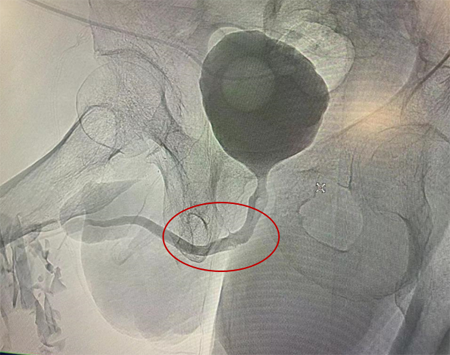

术后1个月,尿道造影示尿道通畅

尿道修复术后1个月,老张回到医院复查,医生为他做了膀胱镜和尿道造影,检查结果显示老张的尿道非常通畅。老张又恢复到他以前自主和自由的排尿。